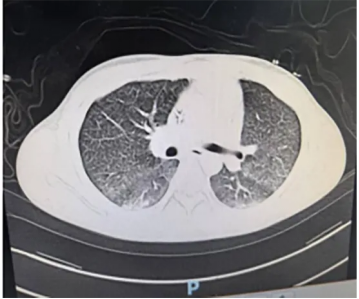

转出时胸部CT